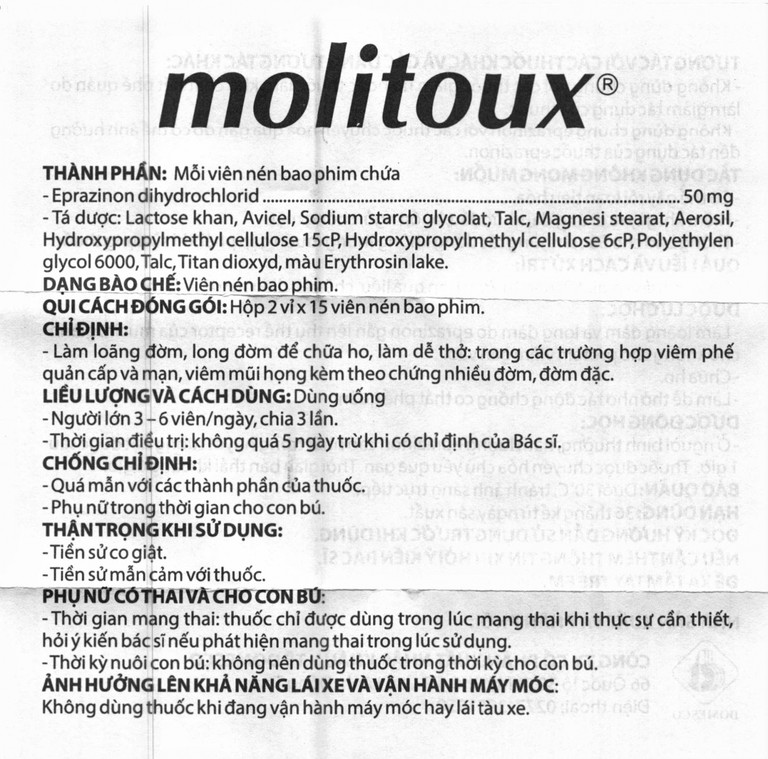

Thành phần của Thuốc Molitoux 50mg

Thành phần cho 1 viên

Công dụng của Thuốc Molitoux 50mg

Chỉ định

Thuốc Molitoux 50 được chỉ định dùng trong các trường hợp sau:

Làm loãng đờm, long đờm để chữa ho, làm dễ thở: Trong các trường hợp viêm phế quản cấp và mạn, viêm mũi họng kèm theo chứng nhiều đờm, đờm đặc.

Cách dùng Thuốc Molitoux 50mg

Cách dùng

Dùng đường uống.

Liều dùng

Người lớn 3 – 6 viên/ngày, chia 3 lẩn.

Thời gian điều trị: Không quá 5 ngày trừ khi có chỉ định của Bác sĩ.

Chống chỉ định

Thuốc Molitoux 50 chống chỉ định trong các trường hợp sau:

-

Quá mẫn với các thành phần của thuốc.

-

Tiền sử co giật.

-

Phụ nữ trong thời gian cho con bú.

Thận trọng khi sử dụng

Người bệnh bị đờm đặc, có mủ hoặc sốt.

Bệnh phổi hoặc phế quản mạn tính.

Thuốc có chứa lactose, người bệnh có vấn đề về di truyền hiếm gặp về chứng không dung nạp galactose, thiếu hụt enzym Lapp lactase hoặc kém hấp thu glucose-galactose không nên dùng thuốc này.

Khả năng lái xe và vận hành máy móc

Chưa có nghiên cứu về ảnh hưởng của thuốc đến khả năng vận hành máy móc, lái tàu xe, người làm việc trên cao và các trường hợp khác. Nếu thấy nhức đầu, chóng mặt khi dùng thuốc thì không nên vận hành máy móc hay lái tàu xe.

Thời kỳ mang thai

Thuốc chỉ được dùng trong lúc mang thai khi thực sự cần thiết, hỏi ý kiến bác sĩ nếu phát hiện mang thai trong lúc sử dụng.

Thời kỳ cho con bú

Không nên dùng thuốc trong thời kỳ cho con bú.